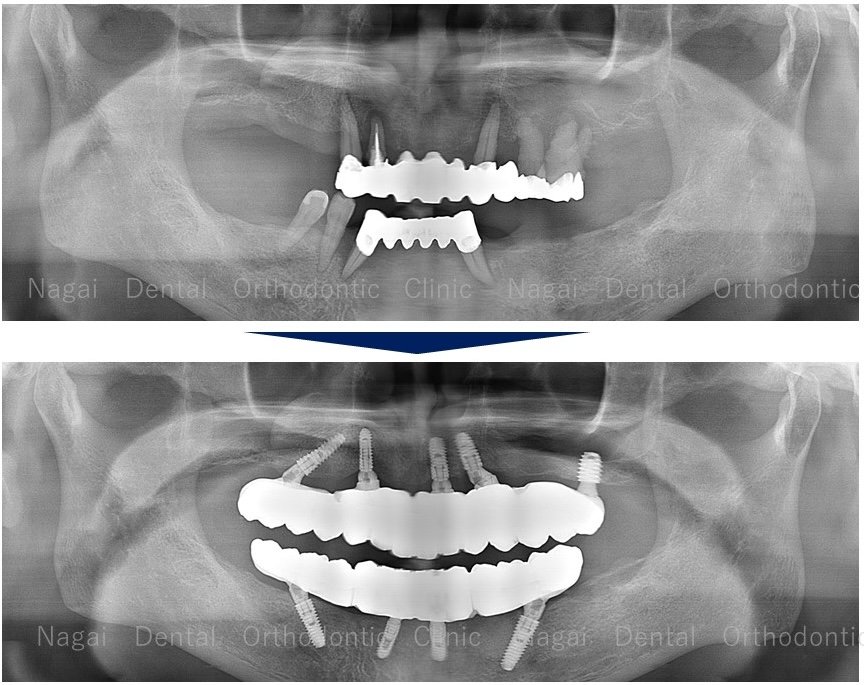

【口腔内の詳細変化】

▲再構築を目的とした治療を行いました

▲欠損していた左上奥歯部分の補綴完了状態

▲支持の安定が期待される治療を行いました

| 治療内容 | 上下オールオン4 |

|---|---|

| 年齢/性別 | 70代/男性 |

| 背景 | 既存補綴物の脱離と広範囲な欠損を主訴に来院。上下顎ともに「オールオン4」を採用し、骨造成を最小限に抑えつつ即日の機能回復を図りました。チタンフレームとジルコニアに加え、歯肉部分も精巧に再現することで自然な口元を構築。安定した噛み合わせにより、食事や会話を心から楽しめる日常を取り戻されました。 |

| 治療期間 | 約16か月(通院8回) |

| 費用 | 6,357,780円(税込) |

| リスク/副作用 | インプラント手術は全身状態や持病によっては適応できない場合があります。また、術後の口腔清掃を怠ると、天然歯の歯周病に似たインプラント周囲炎が起こる可能性があるため、定期的なメンテナンスが必要です。 |